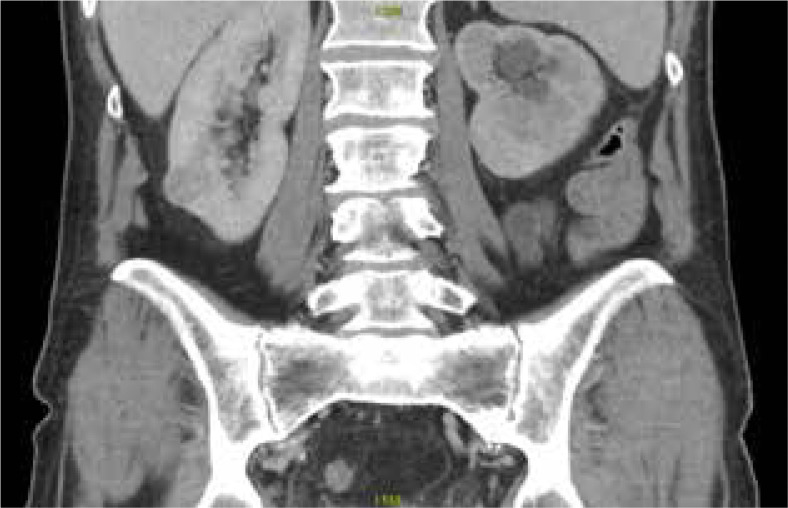

Abstract Image

Purpose: The incidence of renal cell carcinoma has been steadily increasing over the past two decades, raising the need for minimally invasive approaches. We sought to present the methodology of the percutaneous cryoablation (PCA) procedure developed based on one year of experience with 81 PCA procedures.

Material and methods: The percutaneous cryoablation programme at Wroclaw Medical University Hospital has been successfully operating for a year. During this period, patients who were ineligible for partial nephrectomy either because of numerous comorbidities or strong preference against surgery were treated with PCA. Each procedure was conducted with the close cooperation of an interventional radiologist and a urologist.

Results: Over the past year, 81 procedures in 74 individuals have been performed and thoroughly analysed. The mean and median effective radiation doses were 12.57 mSv and 10.76 mSv, respectively. Comprehensive details of our workflow are described within the body of the manuscript.

Conclusions: Percutaneous cryoablation is a technically effective treatment approach for carefully selected individuals with small renal masses. However, starting a PCA programme from scratch necessitates creation of detailed protocols, as well as close interventional radiologist and urologist cooperation. This review outlines the established workflow and shares insights gained from one year of experience with percutaneous cryoablation.